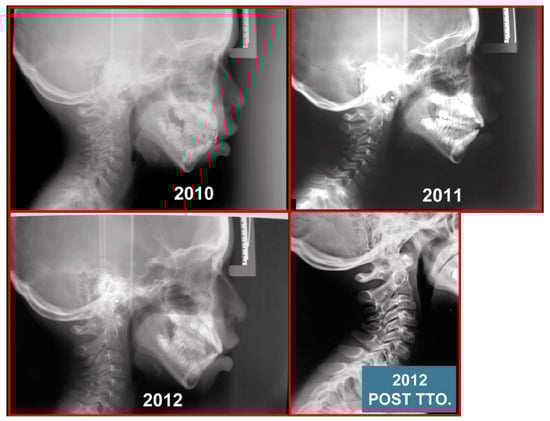

- Rocabado, M.; Gutierrez, R.; Gutierrez, M.F.; Gutierrez, M.J. Case report: Anterior open bite correction treatment by dental treatment and physical therapy through craniocervical mandibular and occlusal stabilization. Cranio 2021, 10, 1–6. [Google Scholar] [CrossRef]